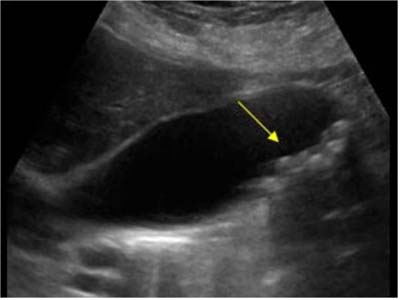

所謂“多發性膽結石”,一般是與“單發結石”區別而論的,就是指膽囊內不僅是一枚膽囊結石,而是可以探及多個或十多個,甚至數十個結石影像,稱為“多發性膽結石”。B超影像中可發現多個強回聲光團,可移動,后伴聲影。

多發性膽結石超聲影像